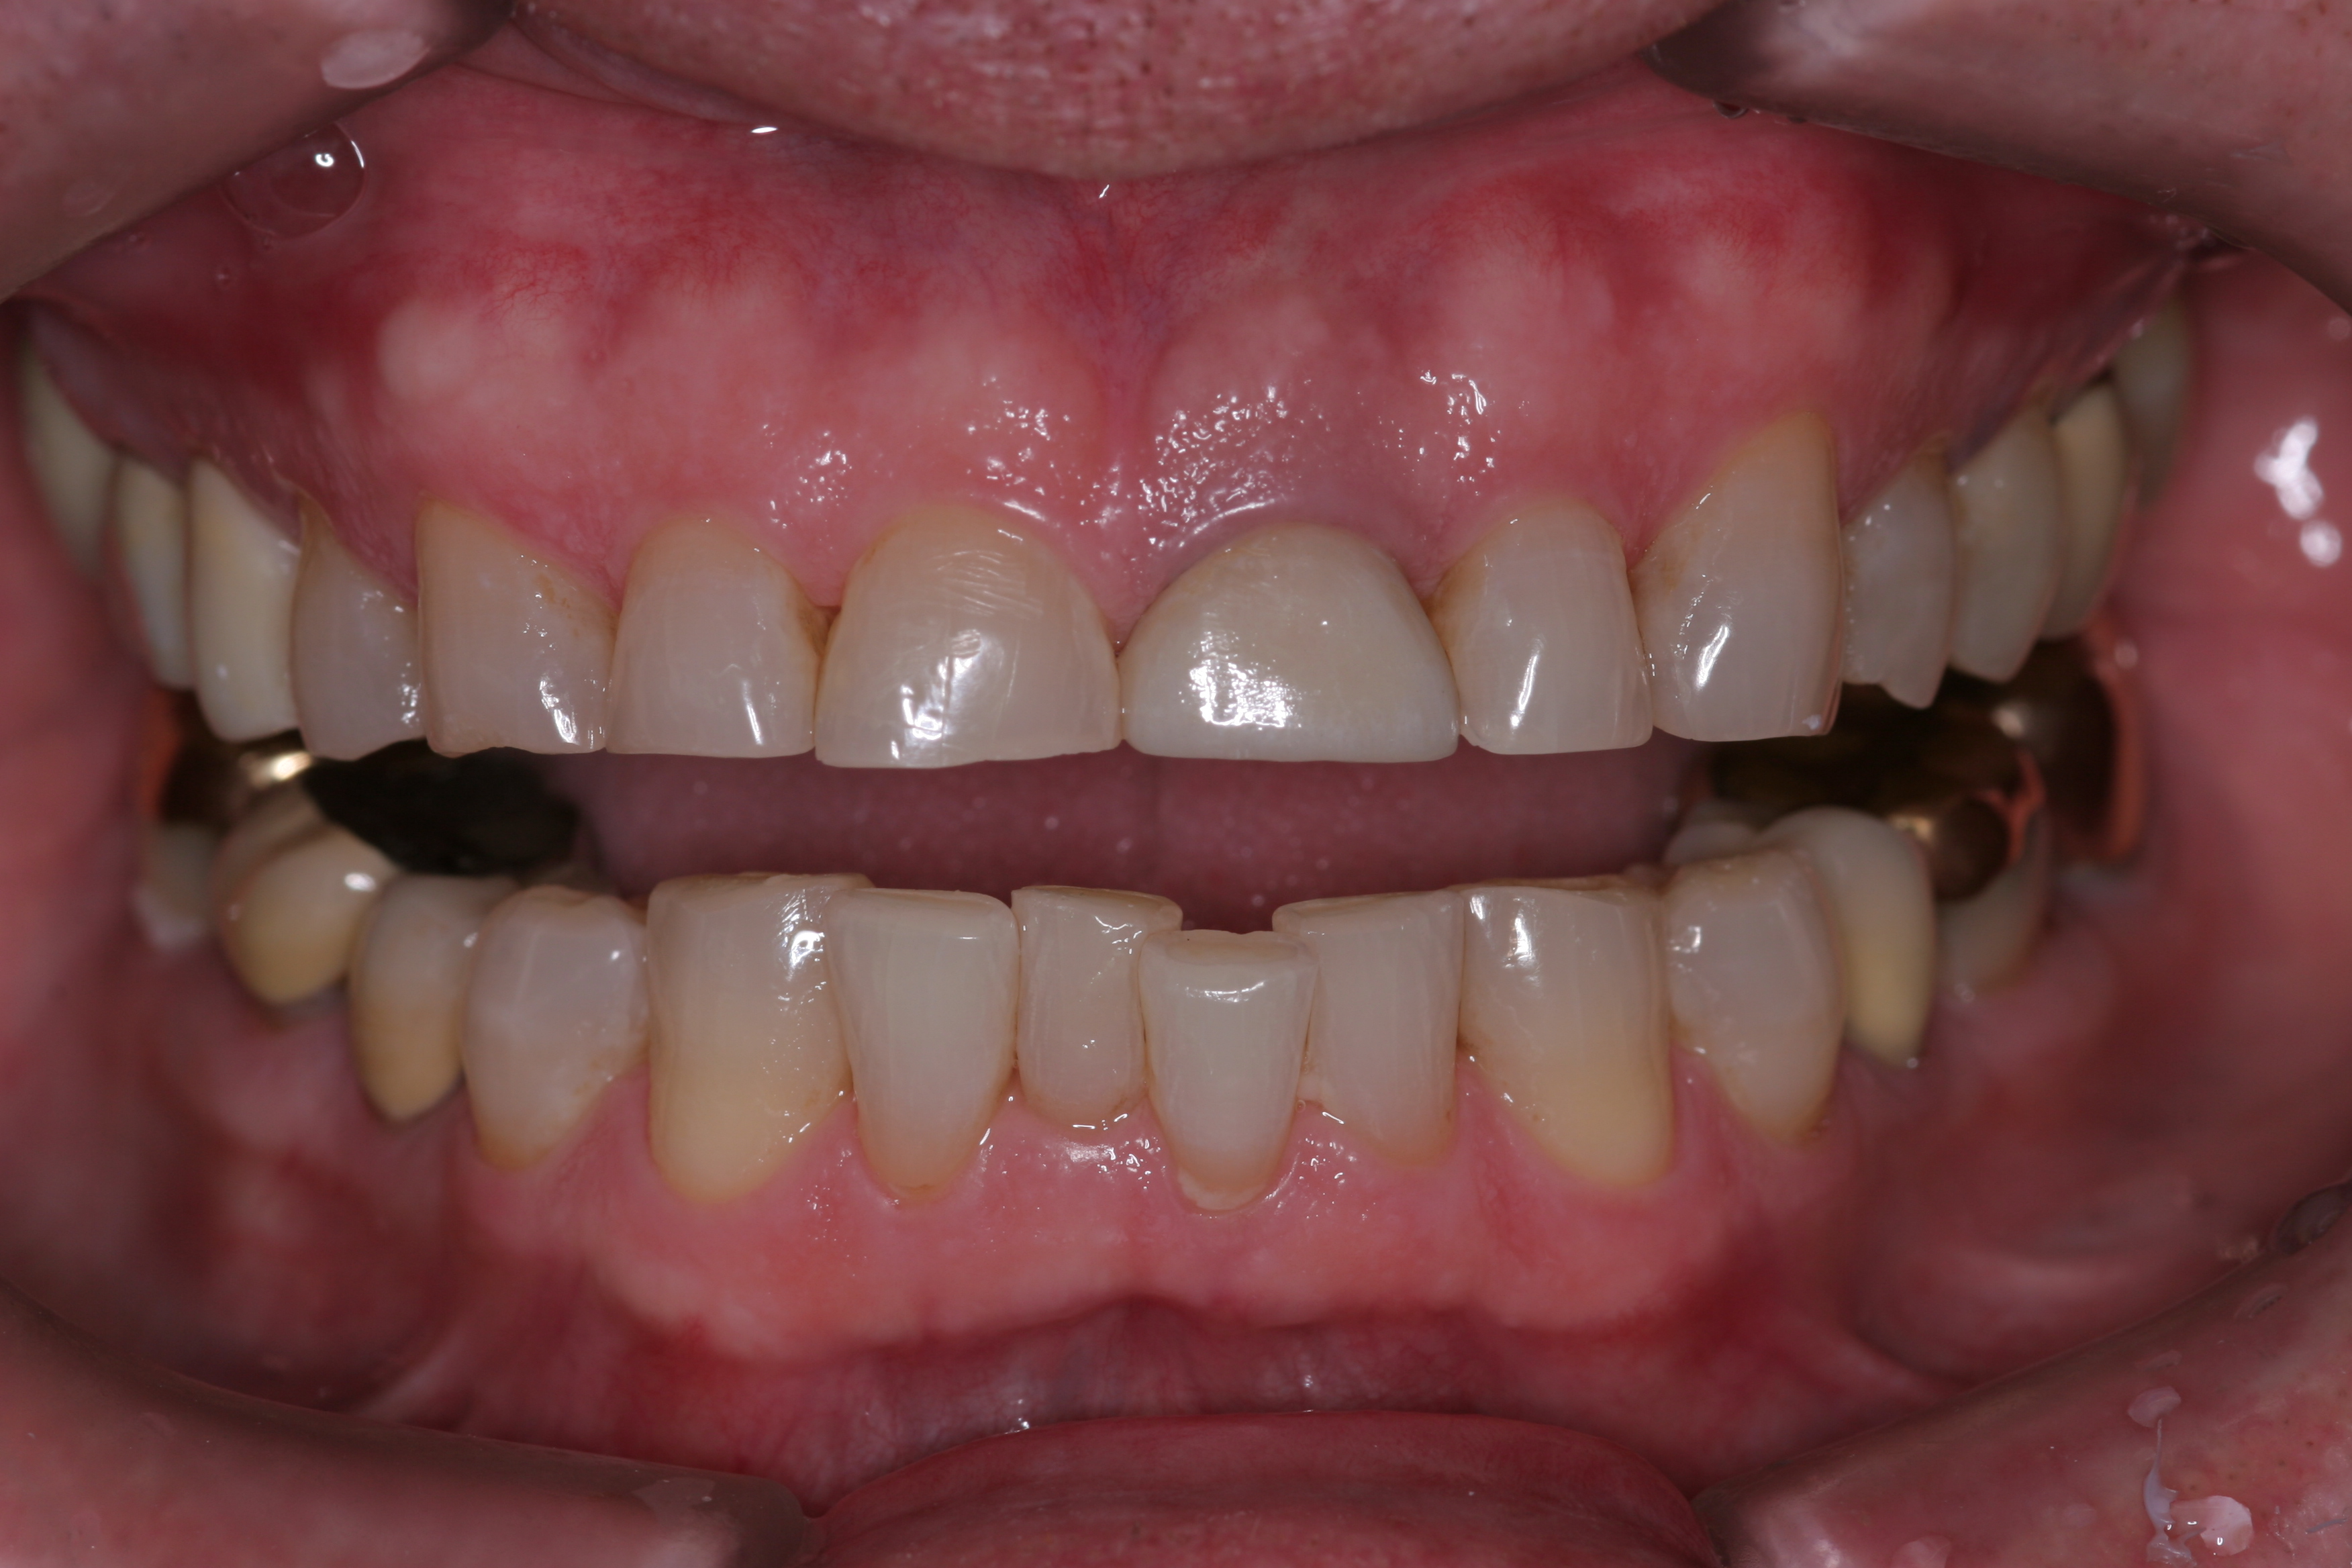

A patient presented with advanced generalized wear of her anterior teeth (Figure 10 and Figure 11). She was displeased with their overall appearance because of their color and wear (Figure 12). A complete examination was performed, revealing instability in her temporomandibular lateral poles bilaterally, sore muscles of mastication, advanced wear, a CR/MIP discrepancy, and loss of her anterior guidance due to the wear. Although the topic is beyond the scope of this article, the patient was also screened for possible sleep apnea. This included an evaluation of the Mallampati score, previous sleep therapy evaluation or treatment, snoring history, an evaluation of her neck size, her weight status, and the presence of the tonsils and their size. In every case, if this clinician suspects airway obstruction to be playing a role in tooth wear issues, the patient is referred to a sleep physician. The patient in this case displayed few apnea risk factors, and the patient’s anterior wear facets fit together like a “lock and key” pattern seen in parafunctional activity. Splint therapy was initiated to stabilize the joints and muscles. A repeatable CR position was verified through load testing. At this point diagnostic models, photographs, a CR bite record, and a facebow were taken and recorded.

(9.) This patient has lost nearly 40% to 50% of his maxillary anterior tooth structure, yet the teeth are still in full intercuspation due to continued eruption as tooth structure is lost due to wear.

Figure 9

(11.) A patient presented with advanced generalized wear of her anterior teeth, and was displeased with their overall appearance because of their color and wear.

Figure 11

(12.) A patient presented with advanced generalized wear of her anterior teeth, and was displeased with their overall appearance because of their color and wear.

Figure 12